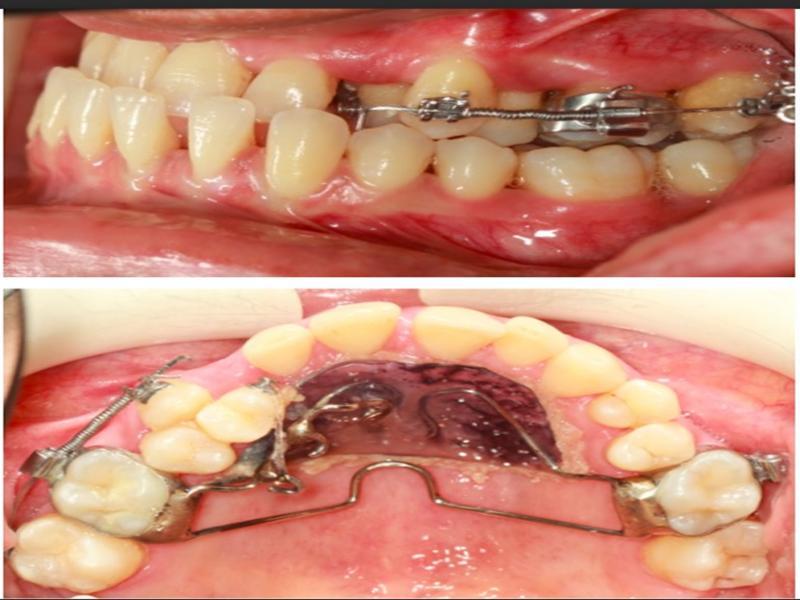

Figure 3.